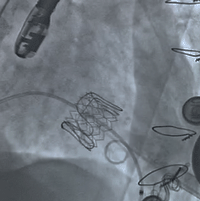

术前经详尽评估患者病情,通过CT重建测量瓣环直径、左室流出道面积。结合之前外科换瓣手术入路,决定采用经心尖途径行二尖瓣“瓣中瓣”手术。术中选用25号Renato®球扩式瓣中瓣,顺利通过心尖途径植入。手术过程顺利,主要操作时间不到半小时,几乎无出血。最终瓣中瓣植入位置理想,功能表现出色,左室造影及经食道超声观察无明显瓣中及瓣周返流。二尖瓣峰值流速由术前2.5m/s降至1.3m/s,平均跨瓣压差由16mmHg降至2.1mmHg。

球扩瓣释放 术后左室造影无反流